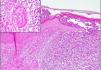

En la biopsia de piel se evidenciaron agregados focales neutrofílicos intraepidérmicos y en la dermis superficial, con extravasación hemática e imágenes de necrosis fibrinoide en pequeñas estructuras vasculares, compatible con VL tipo pustular (fig. 3).